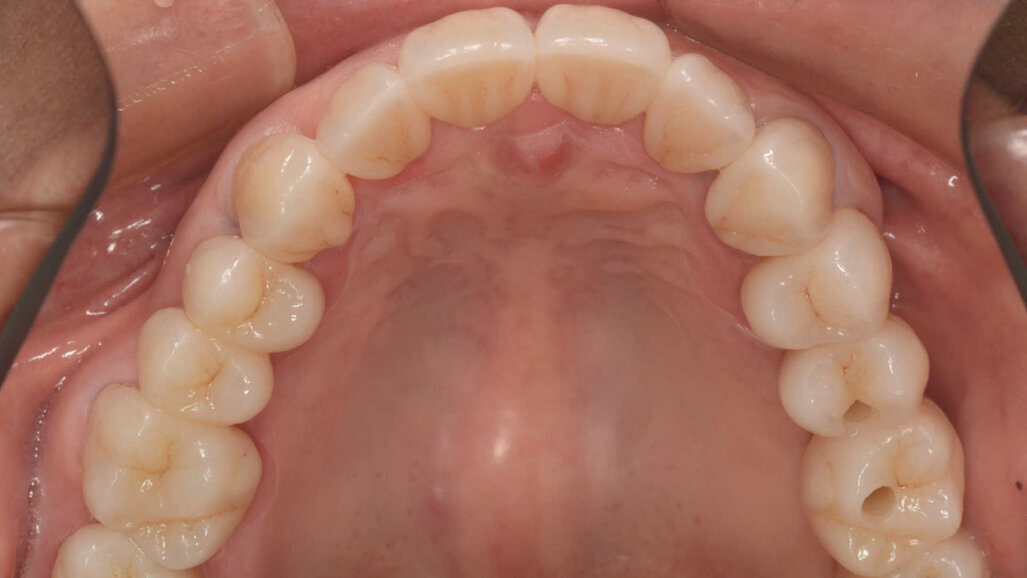

Une patiente de 50 ans atteinte d’une péri-implantite à un stade avancé, s’est présentée à notre laboratoire avec le souhait d’une restauration fonctionnelle et esthétique (Figs. 2a et b). Nous avons établi un plan de traitement qui consistait à traiter la péri-implantite, à poser de nouveaux implants et, finalement, à améliorer l’esthétique générale. Notre première étape a été de reconstruire complètement l’occlusion par une restauration en zircone Zolid FX Multilayer (Amann Girrbach), sauf pour les dents antérieures inférieures.

Fig. 2a : Situation initiale avec péri-implantite à un stade avancé.

Fig. 2 b : Situation initiale avec péri-implantite à un stade avancé.